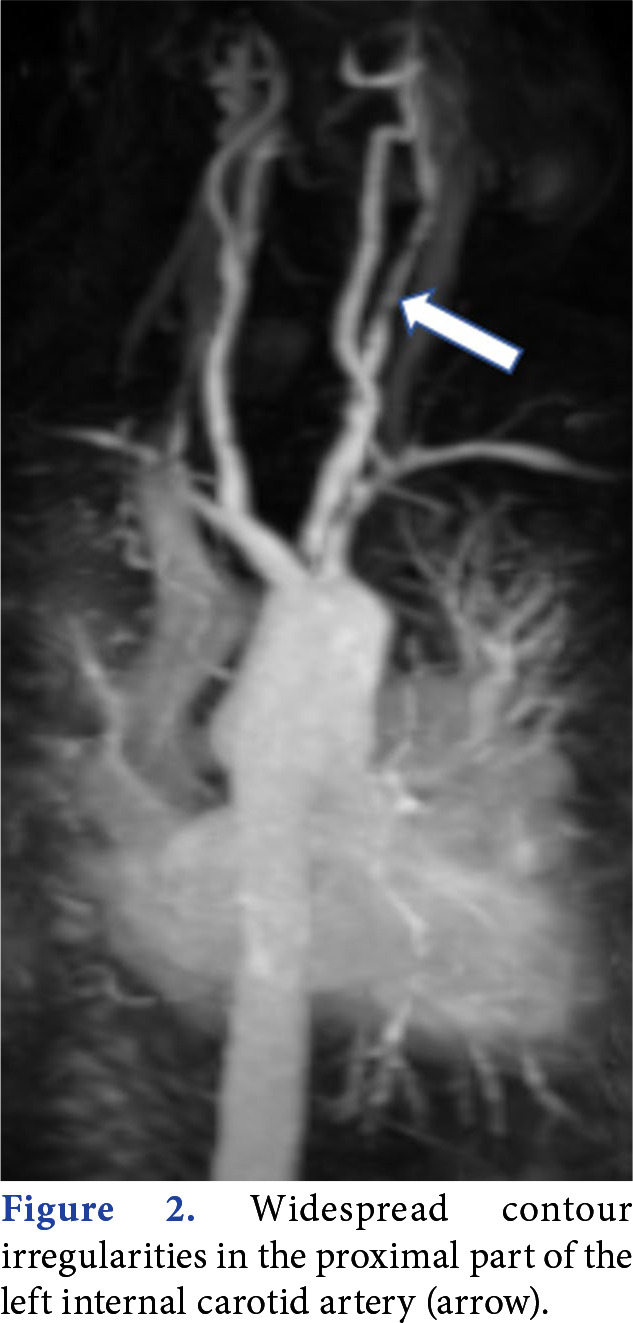

Takayasu arteritis (TA) is an uncommon chronic inflammation of blood vessels. It can occur with a range of clinical manifestations. However, low back pain is uncommonly defined as the initial symptom of TA. In this article, we report a 53-year-old woman who presented with low back pain and was diagnosed with TA after a detailed clinical examination and further evaluations. A thorough history and detailed physical examination can help to recognize the underlying cause of low back pain. Takayasu arteritis should be kept in mind as an alternative diagnosis while evaluating low back pain with high inflammation parameters, particularly in women.